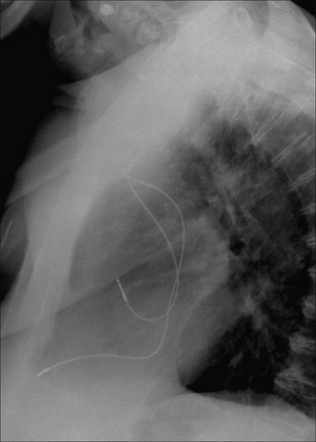

image

Figure 12.5 Optimal electrode positions. Dual chamber pacemaker. Pacemakers tend to be introduced from the left side in right-handed patients.